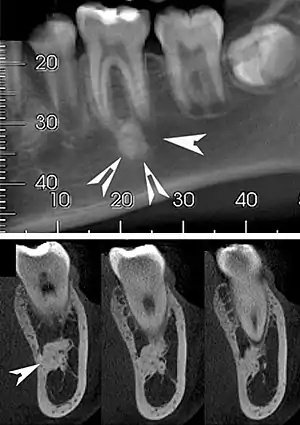

| Top: A hyperdense round lesion located under the apex of a non-infected tooth. Bottom: The lesion is separated from the root of the adjacent tooth by a visible periodontal membrane.[1] | |

Well defined, rounded or triangular radiodensity, that is uniformly opaque. There is no lucent component. Found near the root apex or in the inter-radicular area. Root resorption and tooth movement are rare. If it blends into bone cortices, it does so with no expansion or thinning.[2]